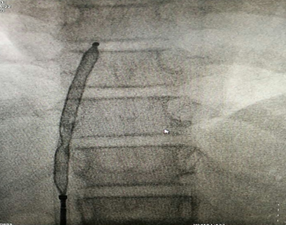

正在释放的封堵器

在征得患者及家属同意后,医院心血管内科手术团队在小章右侧大腿根部做了局部皮肤麻醉,穿刺股静脉成功后,经血管插入一根几毫米的导管,将封堵器送至缺损部位释放。术后立即做心脏彩超及心电图检查,证实无残余分流,无传导阻滞等并发症,手术成功。小章的先天性心脏病得到了“根治”,手术总共耗时约一个半小时。